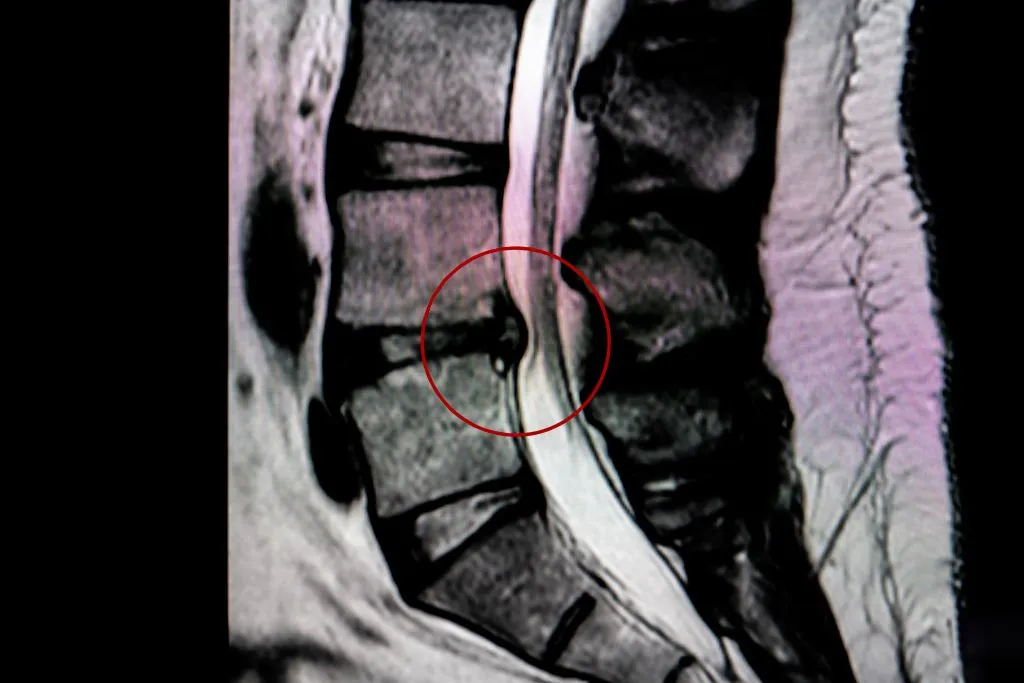

If a herniated disc is suspected, diagnostic imaging is used to confirm the presence of a disc herniation in the lumbar spine at levels L4-L5 or L5-S1.

Deuk Spine’s approach to diagnosing herniated discs involves a unique, highly accurate physical exam designed to pinpoint the exact source of pain. Traditional diagnostic methods that only use MRI scans may not provide enough information to fully understand the cause of pain.

Deuk Spine’s specialized physical exam, which can even be performed remotely through videoconferencing, has a 99% accuracy rate in diagnosing pain sources.